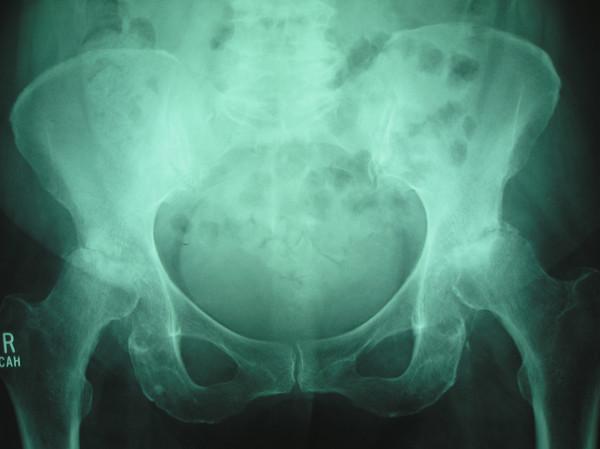

A series of cases from North Wales with rapid progressive joint destruction and extensive subchondral bone loss in the femoral head and acetabulum are presented. Radiographic findings mimicked those of other disorders such as septic arthritis, rheumatoid and seronegative arthritis, primary osteonecrosis with secondary osteoarthritis, or neuropathic osteoarthropathy, but none of the patients had clinical, pathologic, or laboratory evidence of these entities.

Rapid progression of hip pain and disability was a consistent clinical feature. The average duration of symptoms was 1.4 years. Radiographs obtained at various intervals before surgery (average 14 months) in 18 patients documented rapid hip destruction, involvement being unilateral in 13 cases. All patients underwent total hip arthroplasty, and osteoarthritis was confirmed at pathologic examination.